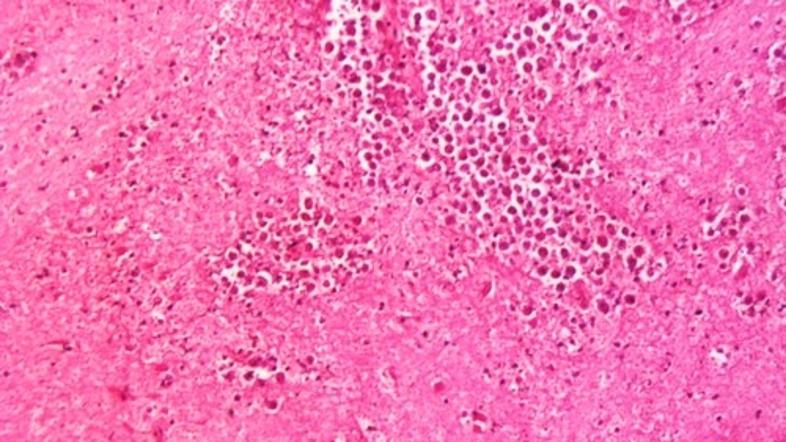

Možganojeda ameba v vodovodu

Ameba Profimedias

Iz tega vodovodnega sistema se oskrbujejo mesta Reserve, Garyville in Mt. Airy. Naegleria fowleri  pri človeku povzroča primarni amebni meningoencefalitis. Ameba povzroči hudo vnetje možganov, razžiranje živčnega tkiva, kar pripelje do smrti v enem do dvanajstih dni po izpostavljenosti amebi. Bakterija najbolje uspeva v topli sladki vodi, najdemo jo lahko v rekah in jezerih. Do možganov potuje preko nosnih membran, s človeka na človeka se ne prenaša.